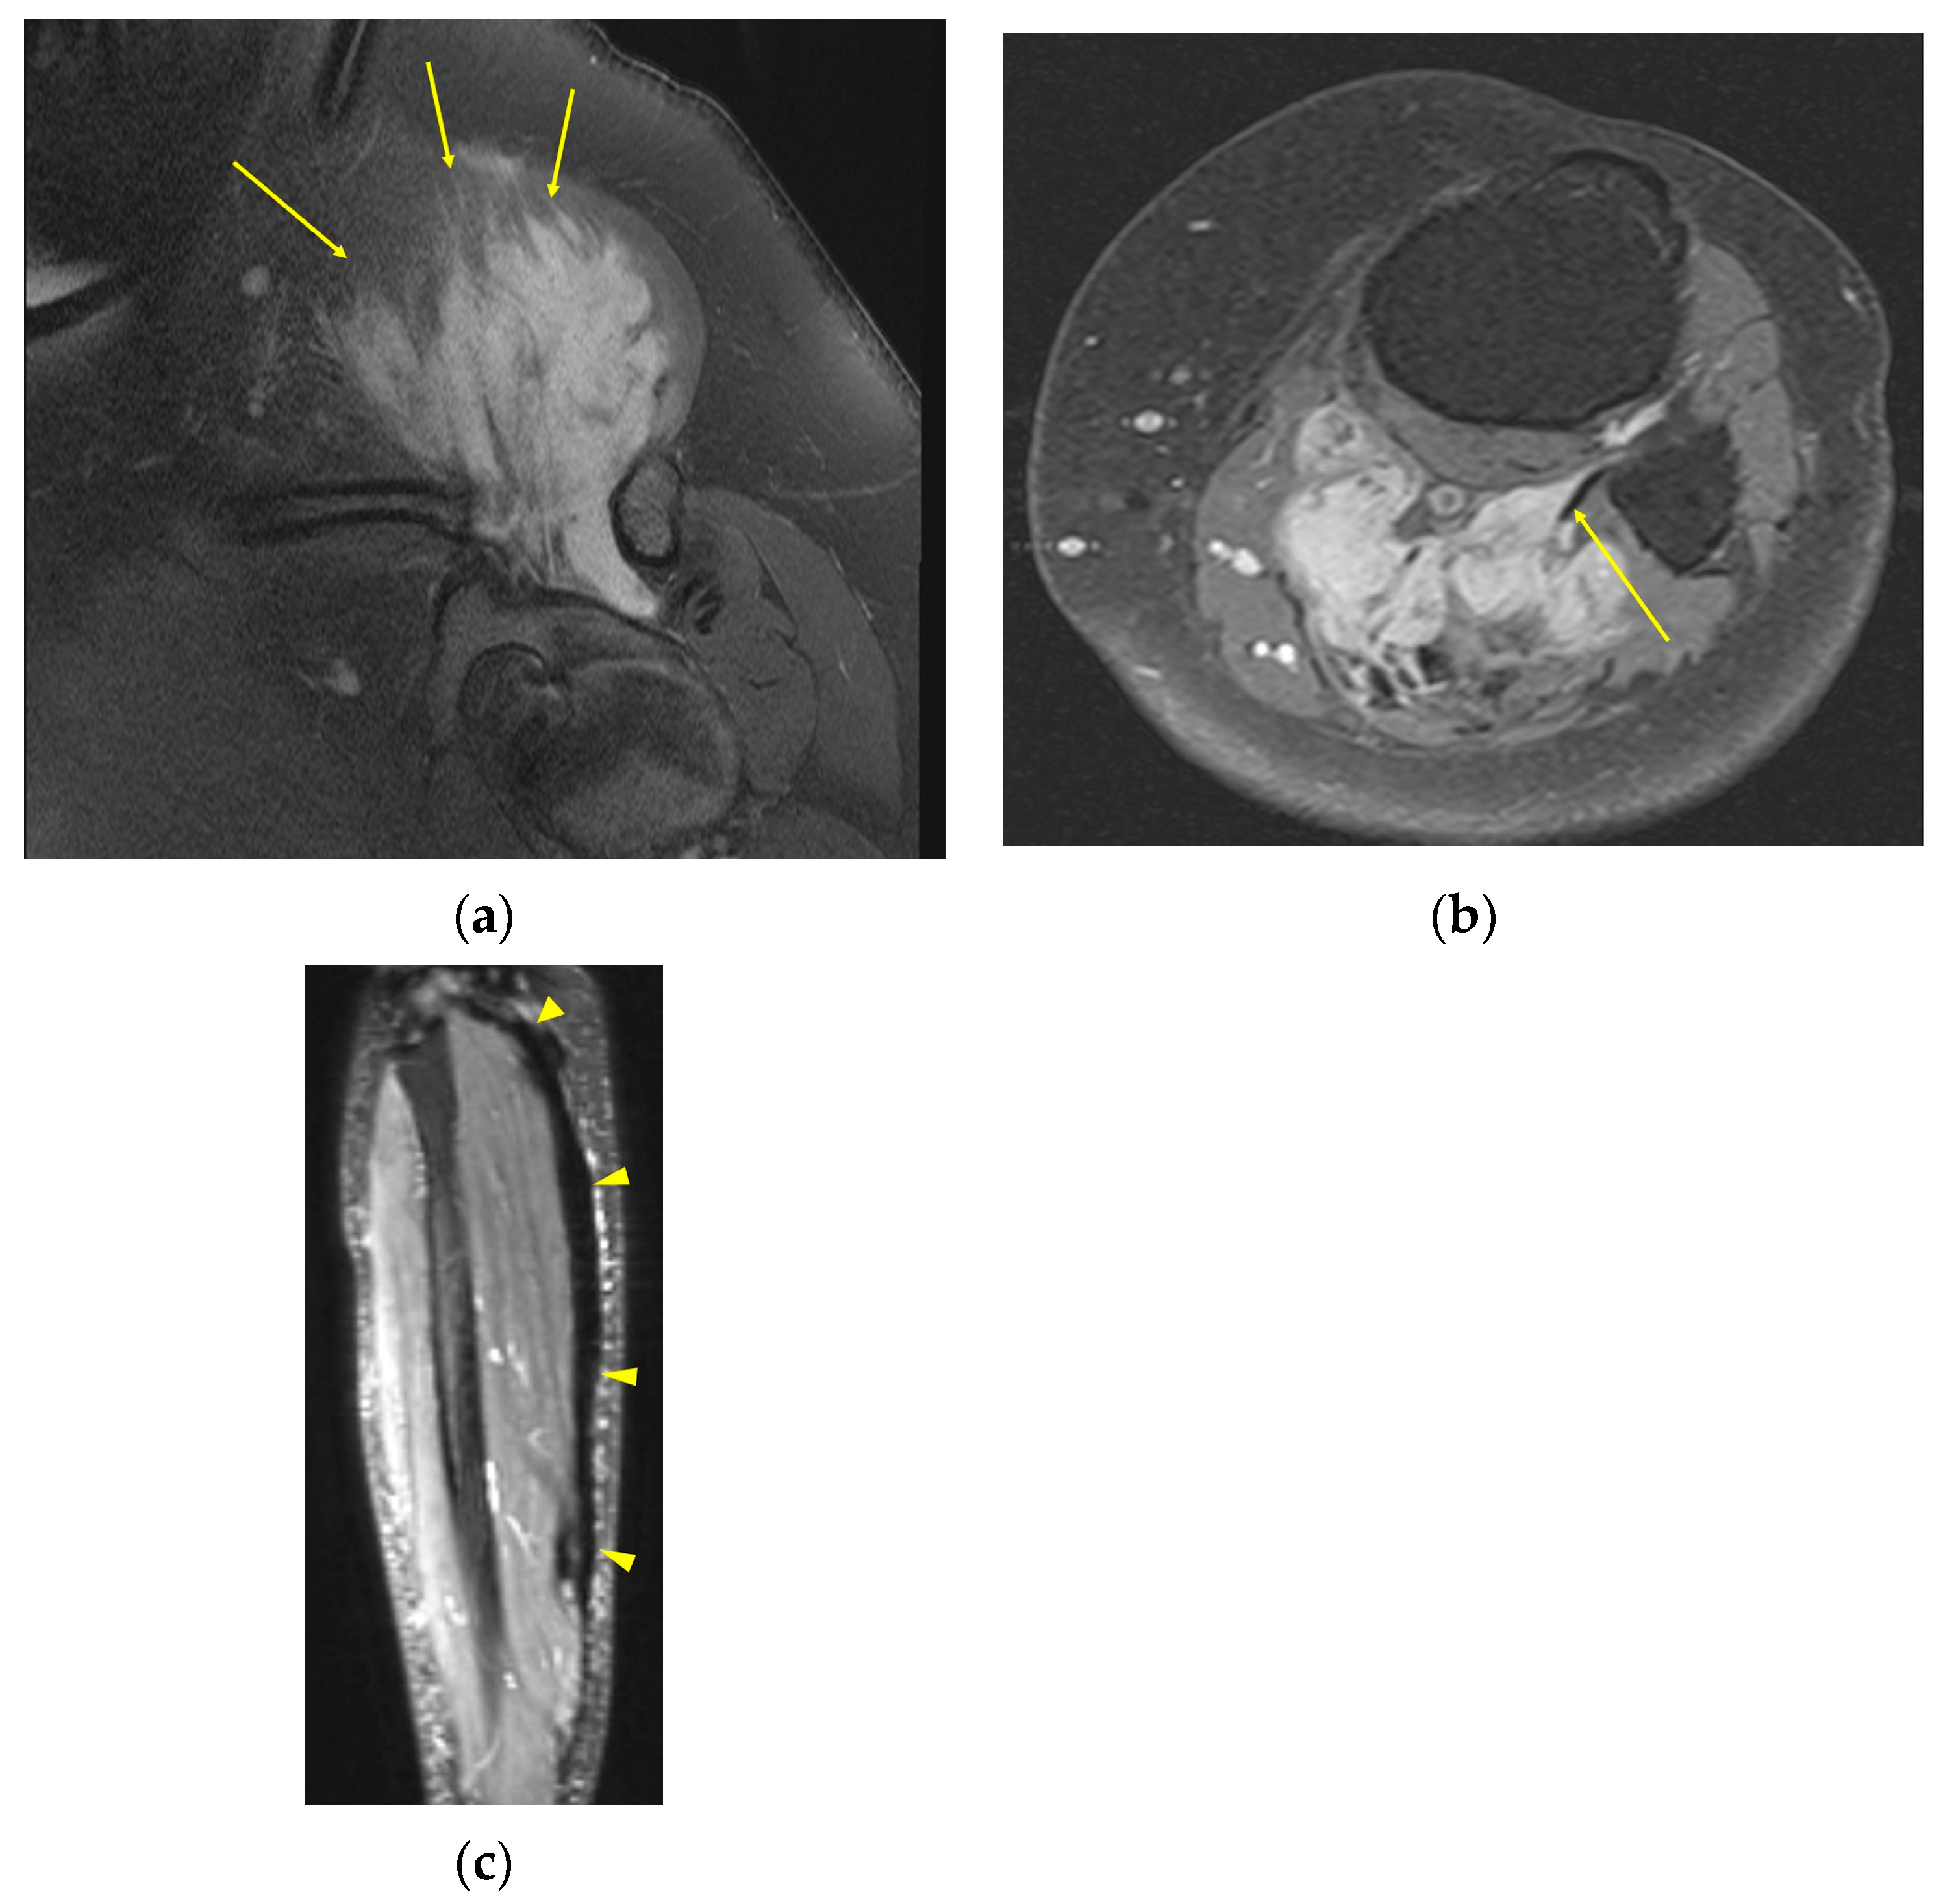

| MRI | Well-circumscribed, heterogenous with nonenhancing T1/T2 hypointense curvilinear areas related to collagen, and T1 intermediate to low/T2 intermediate to high areas related to cellularity or the myxoid matrix. Additional secondary signs (“flame”, “staghorn”, “fascial tail”, etc.) are described in text. |